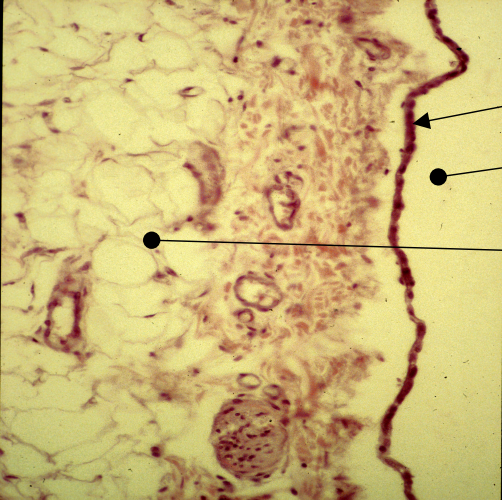

What is shown in the red bracket?

The intimal cushion of the aorta’s tunic intima